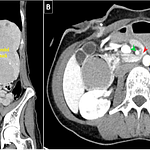

Rodolfo Valentino Syndrome: Perforated Duodenal Ulcer Mimicking Appendicitis

By Joel Joseph, MD and Klaus Mönkemüller, MD, PhD, FASGE, FJGES, FESGE